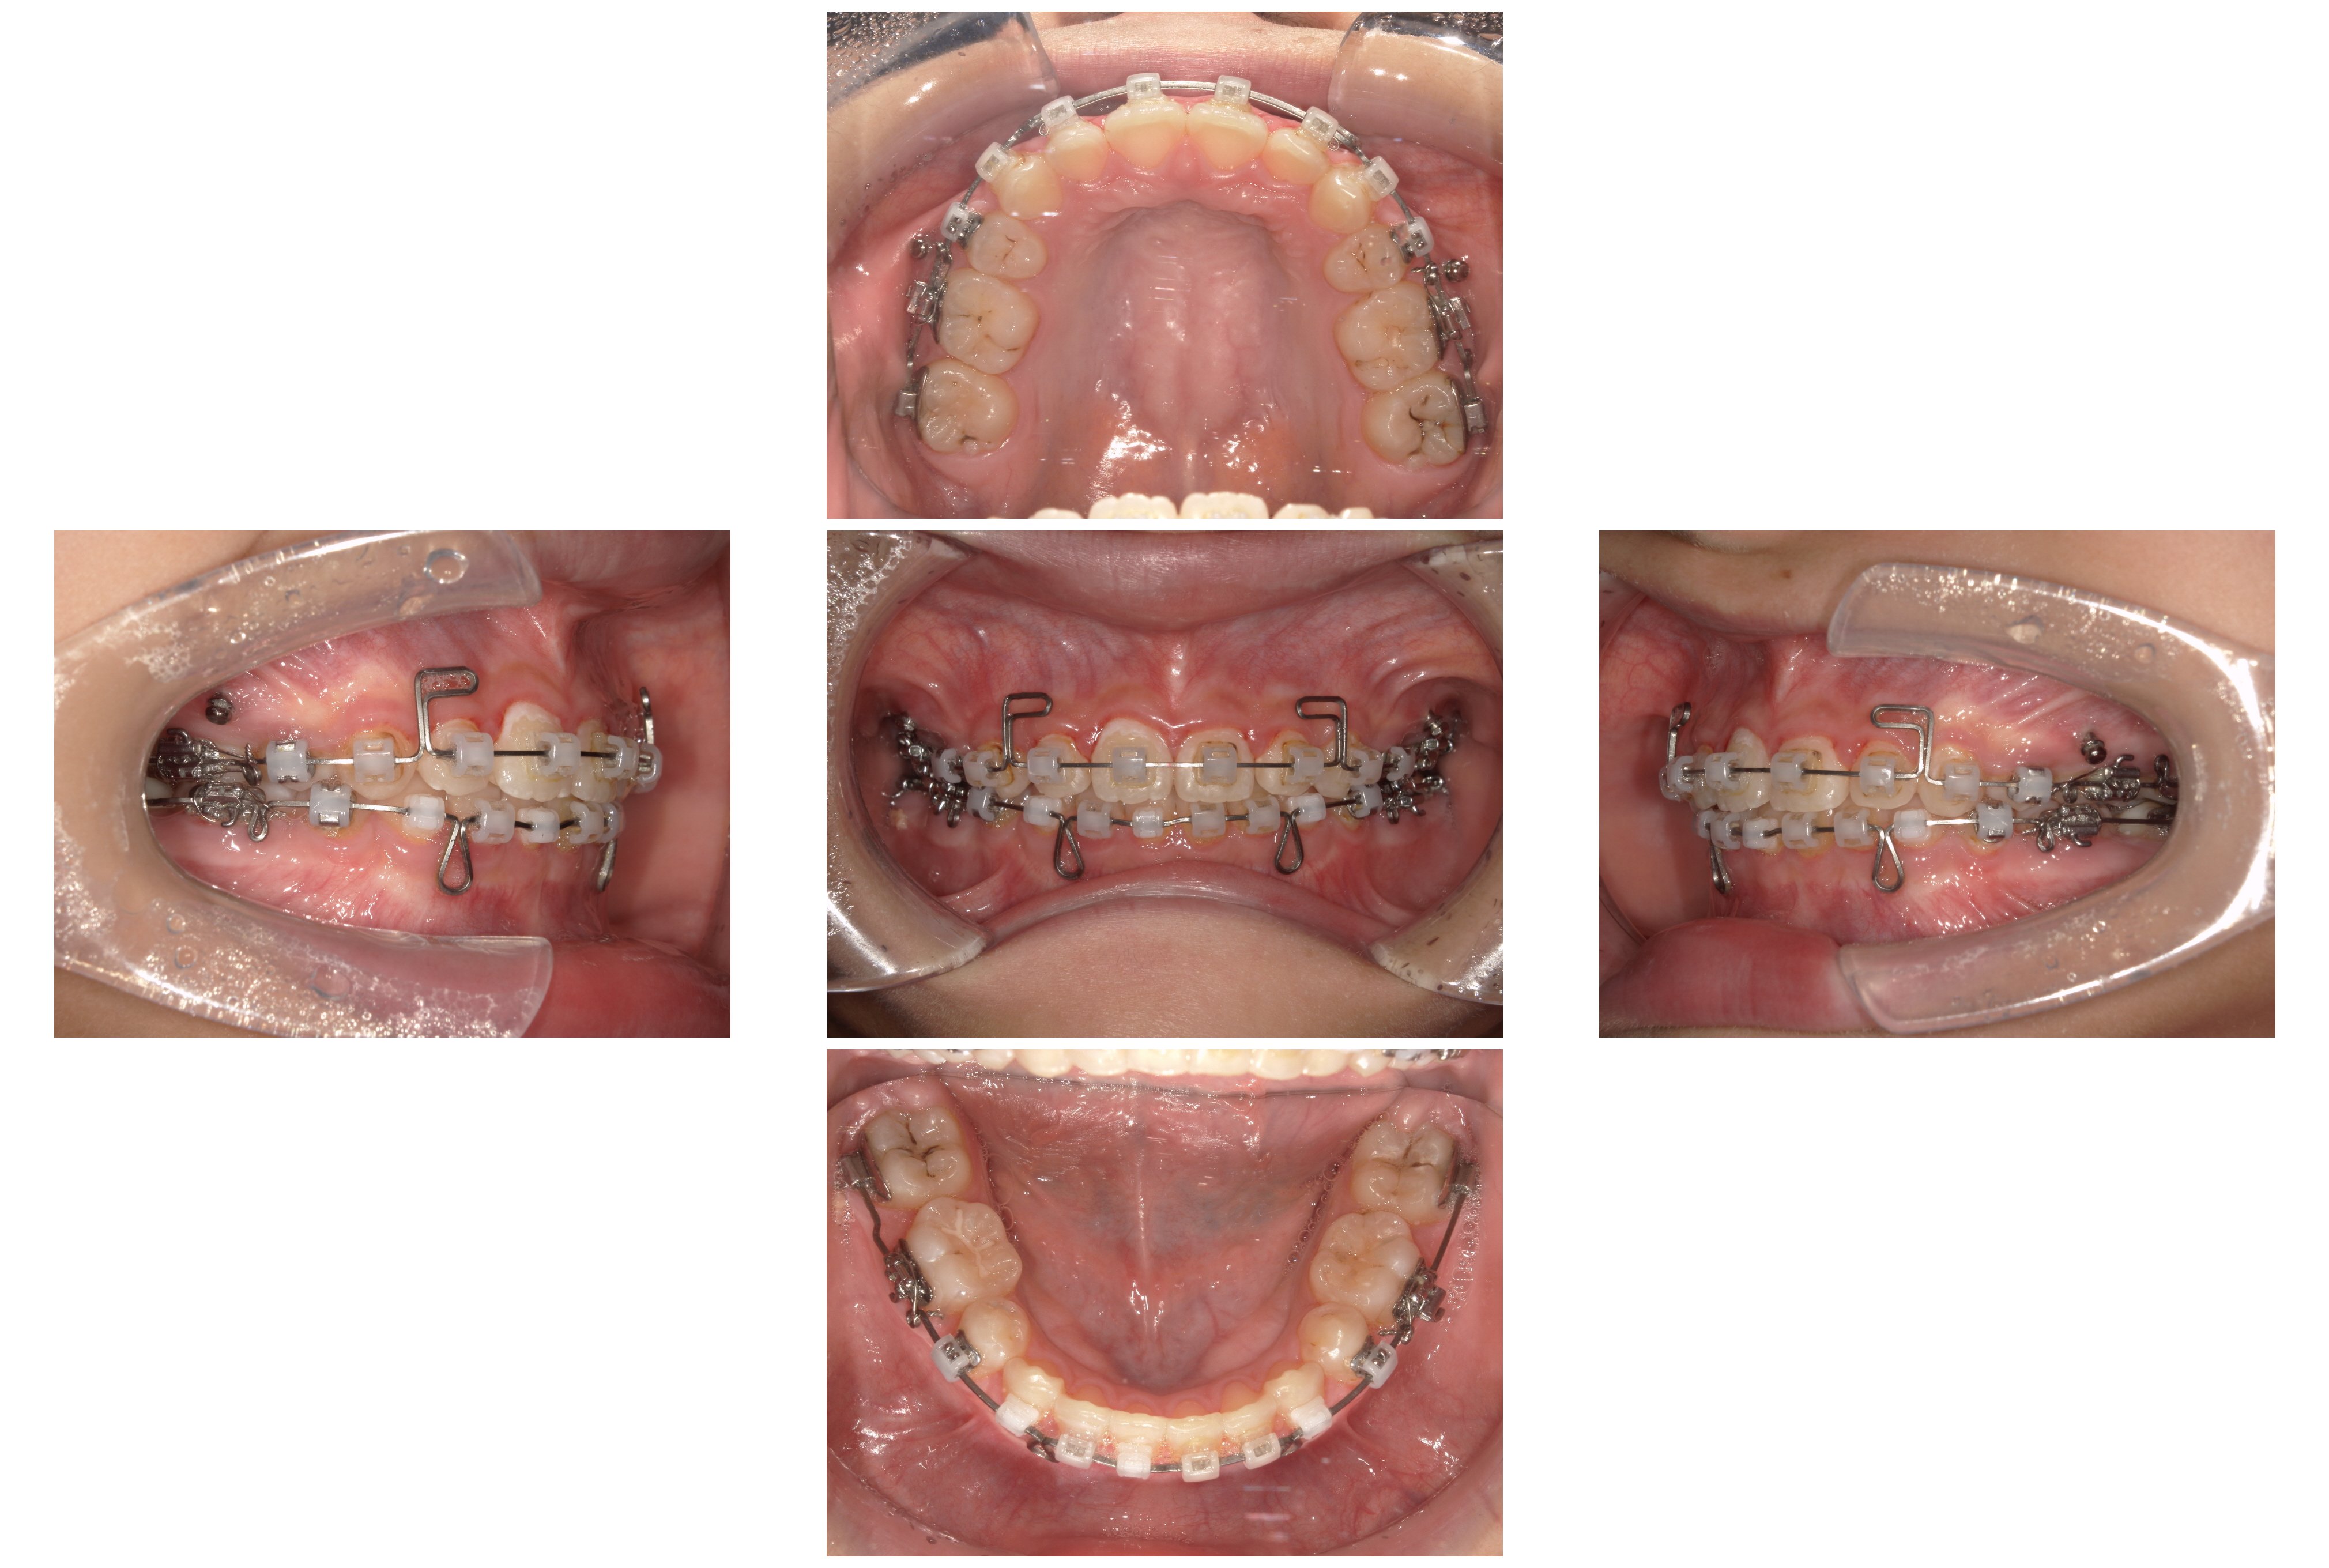

▼2023年12月

③装置装着1年1か月後:こだわりのタイミングでの抜歯

この段階で、事前に根管治療を終えていた下顎左右の5番を抜歯しました。 一般的な矯正では治療開始前に抜歯しますが、本症例では「先に噛み合わせの高さを改善することを優先した」ため、あえてこの時期に抜歯を行いました。